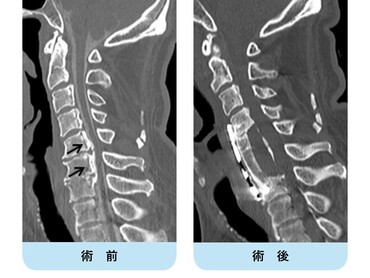

術前MRIでは多椎間で脊髄(灰色)を圧迫しています。後方手術施行後、脊髄への圧迫は改善しています。

頚椎OPLLを認め脊髄を圧迫している状態です。前方からの骨化浮上術により症状は改善しています。

頚椎椎間板ヘルニアを認め脊髄(灰色)を圧迫している状態です。骨移植を伴う頚椎前方固定術により症状は改善しています。